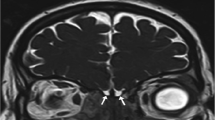

The olfactory threshold trajectories were analyzed exploring the seven threshold test turning points. Typical examples are reported in Fig. 1.

Typical examples of trajectories of olfactory threshold test in a normosmic control (panel A) and three patients with Parkinson’s disease (PD), i.e., a normosmic PD patient (panel B) a hyposmic PD patients (panel C) and a PD patient with functional anosmia (panel D). The symbol ‘X’ marks correct responses, while the symbol – marks incorrect ones. Ellipses around the boxes mark the turning points. Starting with the lowest n-butanol concentration (pen number 16), a staircase paradigm is used. Reversal of the staircase (i.e., the presentation of the triplet with the next lower odor concentration) is started when the odor-containing pen is correctly identified in two successive trials (starting point). Then, when subjects give an incorrect answer, the triplet with the next higher odor concentration is presented and thus, the staircase is reversed again to explore different turning points. Testing is complete after seven reversals of the staircase. Odor threshold final score is calculated as the mean of the last four out of seven turning points of the staircase (marked with light gray shade). Higher and lower olfactory threshold score value represents better and worse performance, respectively

During the first trials, the threshold turning points in PD patients were better than controls (i.e., higher value), then they were comparable to that of controls since the third turning point, then finally worsened (i.e., PD patients showed lower values than controls) for the last trials (Fig. 2). This pattern indicates faster olfactory threshold adaptation in PD than controls. Two-way RM-ANOVA showed significant effect of Turning Point (F[6,522] = 45.1; p < 0.001) and significant Turning Point × Group interaction (F[6,522] = 6.5; p < 0.001), but no effect of Group (F[1,87] = 0.2; p = 0.62) when comparing MA-PD and controls for odor threshold turning point trajectory. Post hoc analyses showed that detection threshold value was significantly lower in MA-PD patients than controls at the last turning point (p = 0.005; Fig. 2A).

Olfactory threshold at the seven turning points (TP) in controls (N = 60; open boxes) and Parkinson’s disease (PD) patients with age < 70 years (MA-PD; N = 31; closed boxes; panel A) and PD patients (PD; N = 59; closed boxes; panel B). Higher and lower olfactory threshold score value represents better and worse performance, respectively. *Marks significant patients vs. controls comparison